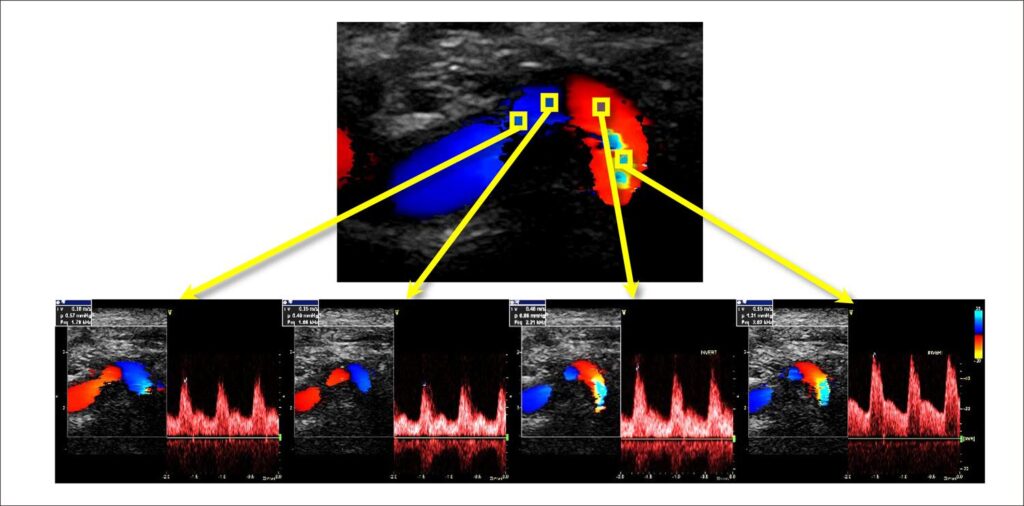

My Approach To: Vascular Ultrasonography in Dolichoarteriopathies of the Carotid Arteries

This article provides step-by-step guidance on how I investigate, classify and evaluate dolichoarteriopathies anatomically and hemodynamically, often found in the carotid and vertebral arteries. Dolichoarteriopathies may be present in children, disappearing during growth and reappearing with increasing age. Previously considered benign anatomic variations (AVs), discussion has arisen on the topic in view of new implications due to associations with cardiovascular events, risk factors, and various pathologies.